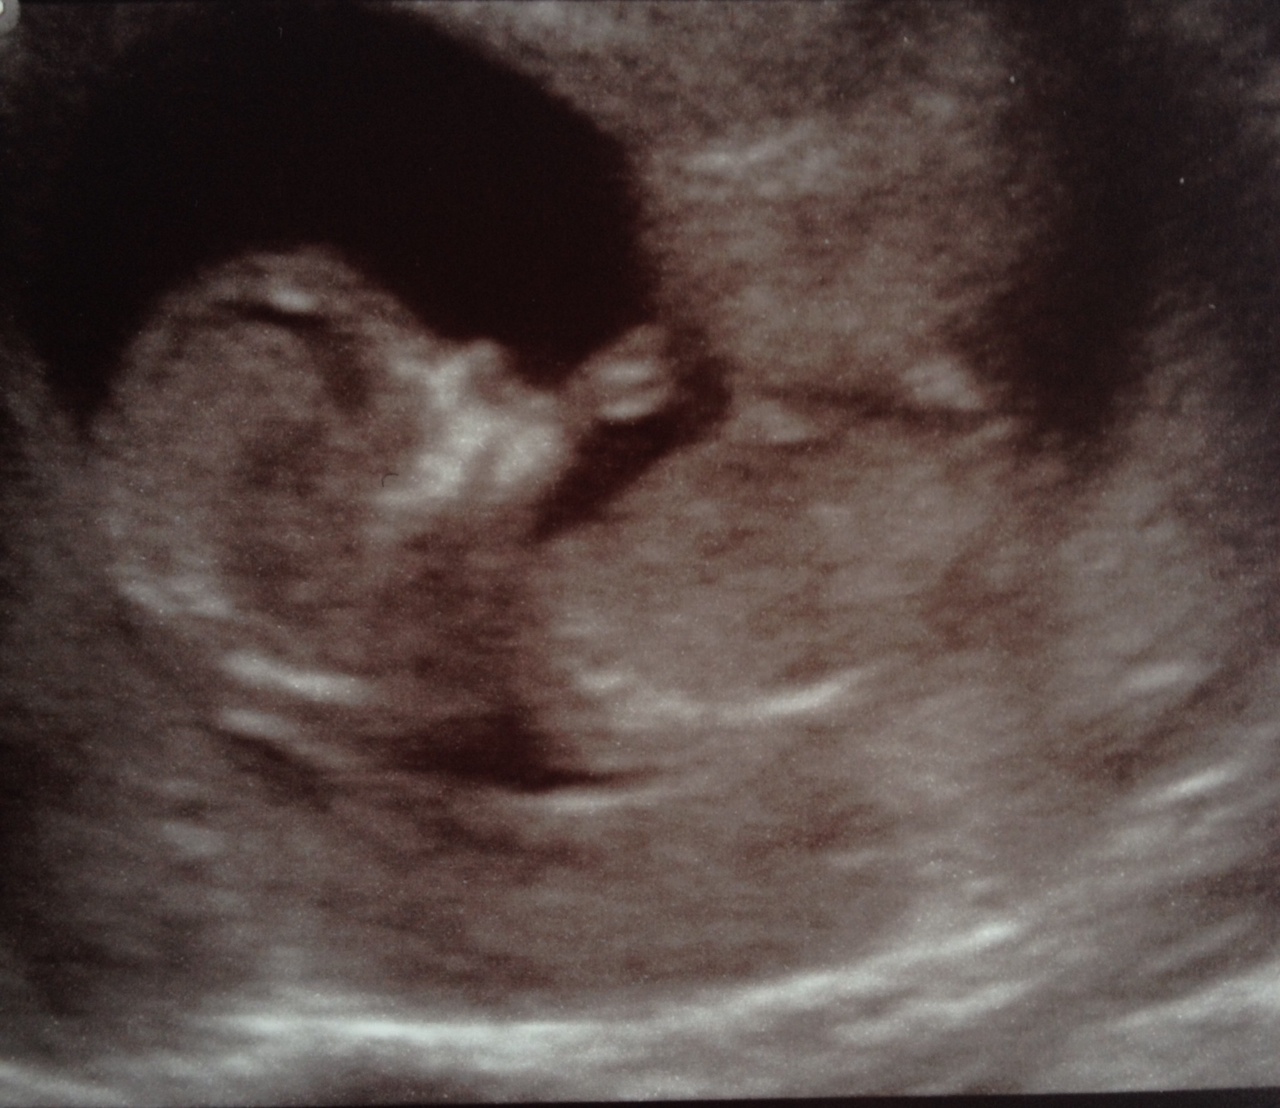

You can just about make out the nub there but the end is rather blurry. Overall it looks relatively flat and possibly extends past the bum making it more girly but if there is a bump on the top then obviously it would look more boyish. Overall I have to say I am still 50/50. Some people have a theory that more curled up babies are girly but the curve in the spine can make a nub appear flatter than it really is. Xx

I'll post a couple of other pics in case they help but I'm not sure that they will. Thanks again!